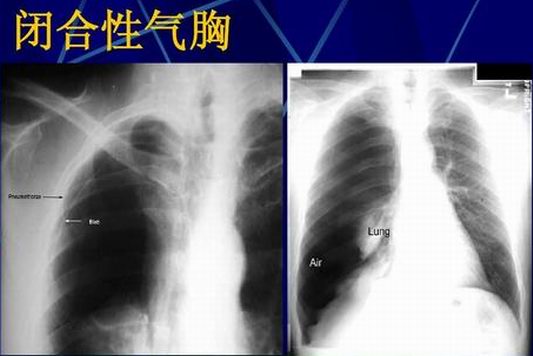

(1)闭合性气胸

又称单纯性气胸,胸膜破裂口较小,会随肺萎缩而闭合,呼气和吸气过程中,空气不再进入胸膜腔。

1、胸部X线摄片

是检查气胸的重要方法,可以显示肺部受压或病变情况以及有无胸膜粘连、胸腔积液等并发症。气胸时,可看到外凸弧形的气胸线;大量气胸时,肺组织受压呈圆球形阴影。